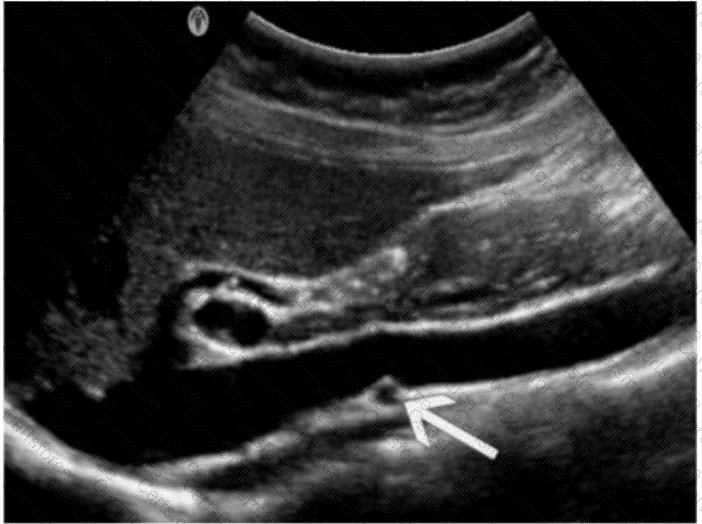

The ultrasound image demonstrates a transverse view of the abdominal vasculature, where the arrow is pointing to a circular vascular structure anterior to the aorta and posterior to the body of the pancreas — consistent with the superior mesenteric artery (SMA).

The SMA originates from the anterior aspect of the abdominal aorta just below the level of the celiac trunk and courses anterior to the left renal vein and uncinate process of the pancreas. On transverse ultrasound, it is often seen in cross-section as a round, pulsatile structure with echogenic walls, situated just anterior to the aorta. This appearance is known as the “target sign” or “bull's-eye” appearance.

Vessel Position Landmarks (transverse plane):

Aorta: Posterior and central

SMA: Just anterior to the aorta

Left renal vein: Passes between the aorta and SMA (nutcracker location)

Right renal artery: Courses posterior to the IVC toward the right kidney